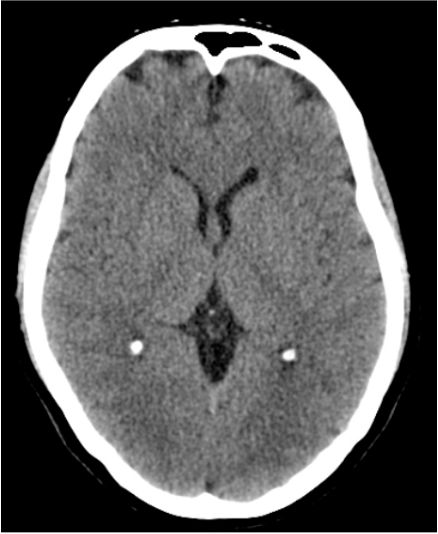

Normal brain CT – but symptoms already warn us!

• This image shows a healthy brain – there are no visible signs of damage.

• Yet, if someone suddenly develops weakness on one side, has slurred speech or clumsiness, the doctor knows: a stroke may be to blame!

• In the earliest phase, CT often looks normal, but treatment must start based on symptoms—not just imaging.

• The only chance is getting to hospital and medical care as quickly as possible.